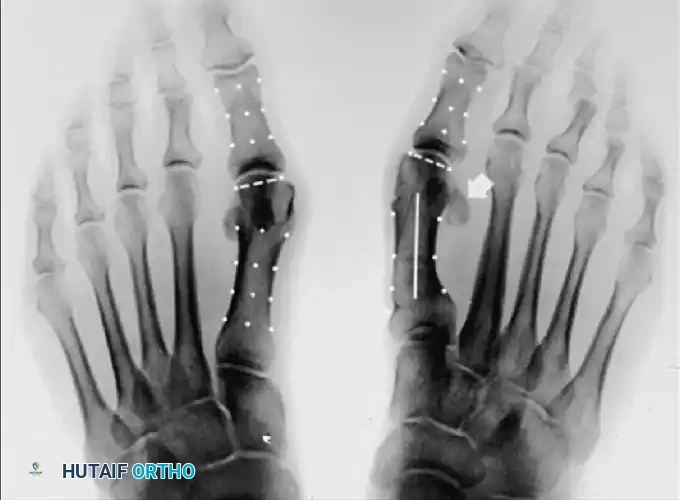

Standard weight-bearing anteroposterior (AP), lateral, and sesamoid axial radiographs are mandatory. Surgical decision-making relies heavily on precise angular measurements.

Key Radiographic Parameters

• Hallux Valgus Angle (HVA): The angle between the longitudinal axes of the first metatarsal and proximal phalanx. Normal is < 15°.

• Intermetatarsal Angle (IMA): The angle between the longitudinal axes of the first and second metatarsals. Normal is < 9°.

• Distal Metatarsal Articular Angle (DMAA): The angle between the articular surface of the first metatarsal head and the longitudinal axis of the metatarsal shaft. Normal is < 10°. An increased DMAA indicates a congruous joint in a valgus position, necessitating a specific intra-articular or extra-articular corrective osteotomy.

Surgical Warning: Failure to recognize an abnormal DMAA will lead to undercorrection or early recurrence. If a standard proximal osteotomy is performed without addressing the valgus articular orientation, the joint will remain congruous in valgus, and the deformity will persist.